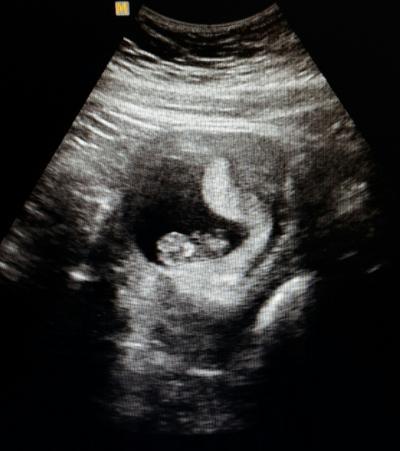

Hallo ihr lieben! Klar hab ich keine Schlange im Bauch aber was ist auf meinem US zu sehen??? Zysten habe ich keine. Habe den Arzt auch nicht drauf angesprochen, habe ich nicht dran gedacht in dem Moment. :) Danke für eure Antworten. Glg :)

Bild zu Schlage im Bauch ;)? US Profis sind gefragt - Schwanger - wer noch? Rund um die Schwangerschaft

Hallo du, also ich sehe da ein Baby ! Was die "Schlage" sein soll weiss ich nicht ,aber auf jeden Fall ein Baby vielleicht in der 8-9 SSW ? Aber ich denke das Du schwanger bist weist du sicherlich schon ...... Würde deinen FA einfach mal fragen was die "Schlange " da sein soll.lg

Ja das ich schwanger bin weiß ich :) die woche stimmt auch. Ich meine dieses Gebilde was neben dem baby bei den Füßen so nach oben geht und ebenfalls so hell ist. Ich dachte das einzige das man in der GM als hell sieht ist das baby, aber da ist ja nochwas....:-/ Ich werde das nächste mal die Ärztin fragen. Wenn es noch so zu sehen ist. Hatte nur bedenken das sie mir evtl was verschweigt das mit der GM etwas viell. nicht stimmt. Ich wurde nämlich auch von einer Freundin gefragt die im fünften Monat ist, was das neben dem Kind wäre. ...

Mach dir mal keine Sorgen,ich denke es ist alles ok.So ein US Bild sieht halt manchmal auch immer etwas komisch aus.Es könnte auch einfach Fruchtwasser sein ,was durch die Bewegungen die dein Körper macht dann im US Bild aussieht wie eine Schlange.....ich hab leider auch keine Ahnung was es sein soll,aber ich gehe davon aus wenn es was schlimmes wäre oder etwas was so nicht sein soll dann hätte dein FA dir das gesagt.